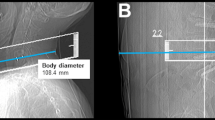

Parameters obtained from SD and LD scanning included the dose length product (DLP), volumetric CT dose index (CTDIvol), number of scans required to perform the spine biopsy (periprocedural guidance scans via sequential scanning), and measurements of body diameter. The individual body diameter was measured in the lateral scout scan at the level of the planned intervention and was determined from skin-to-skin surface (Fig. 1)23.

Exemplary patient cases for a L3 bone biopsy for a suspected bone tumor in a 77-year-old male using scanning with standard dose (SD; A) and a L1 bone biopsy in a 49-year-old woman with a suspected bone metastasis from known breast cancer using scanning with low dose (LD; B). The scans were rated with excellent image quality and high confidence.